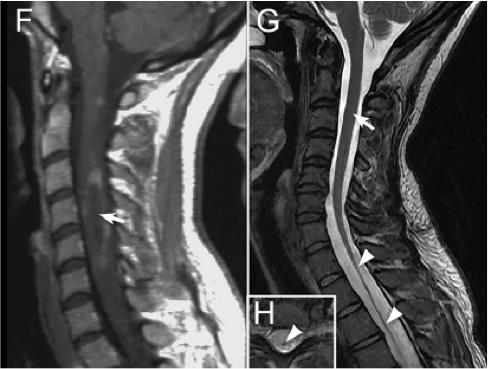

二、影像特征 1. NMOSD 脊髓MRI:长节段的脊髓炎(≥3个节段),呈中心分布,横贯性

2. NMOSD 视神经MRI:病变较长,累及视交叉